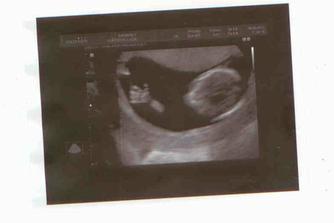

30.03. - (20+5), tak na dnešní kontrole dopadlo všechno na 1*, vážíme už 380g a z našeho Marečka se nakonec vyklubala Amálka, která měla mezi nožičkama zamotenej pupečník 😀 Pan doktor říkal, že tentokrát, je to opravdu na 100%